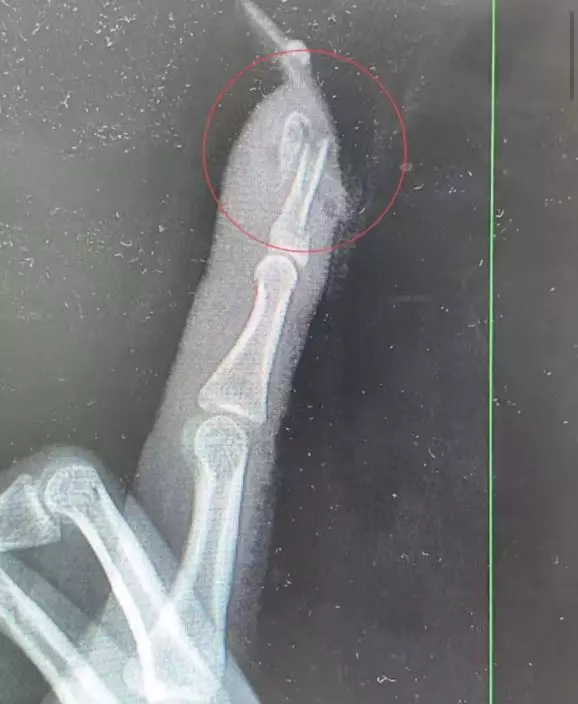

王小姐之後到杭州市臨平區中西醫結合醫院骨科求診接,診醫生曹立檢查後證實,她的左手食指指骨骨折、甲床破裂,部分組織外露,需要接受手術修復。醫療團隊即時為她進行指骨骨折閉合復位內固定術,術後恢復情況理想。

延長甲片產生槓桿效應 加劇受傷程度

曹立指出,若沒有貼上細長複雜的延長甲片,傷勢或未必如此嚴重。他解釋,延長甲片會增加手指受力面積及槓桿效應,跌倒時更容易形成撬動力量,導致指甲撕脫且甲床受損,甚至引發骨折。